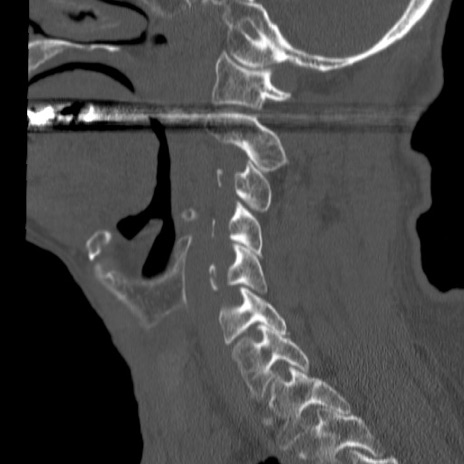

症例46 頚椎CT(矢状断像)

【症例】80歳代男性

【主訴】両側頚部〜上肢のしびれ

【現病歴】昨日、自宅内で転倒、その後より上記症状あり。意識障害なし。

【身体所見】両側上肢のallodynia(熱痛覚過敏)あり。MMTおよびDTRは正確な所見取れず。両上肢の挙上はなんとか可能。

異常所見と診断は?